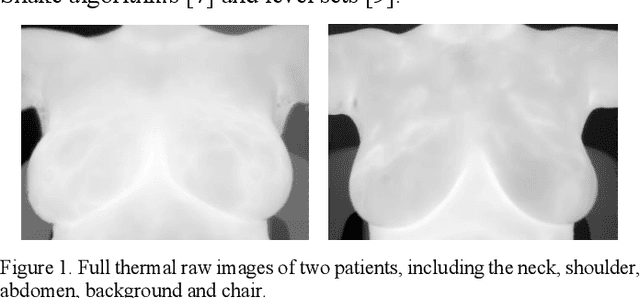

Breast cancer is the second leading cause of death for women in the U.S. Early detection of breast cancer is key to higher survival rates of breast cancer patients. We are investigating infrared (IR) thermography as a noninvasive adjunct to mammography for breast cancer screening. IR imaging is radiation-free, pain-free, and non-contact. Automatic segmentation of the breast area from the acquired full-size breast IR images will help limit the area for tumor search, as well as reduce the time and effort costs of manual segmentation. Autoencoder-like convolutional and deconvolutional neural networks (C-DCNN) had been applied to automatically segment the breast area in IR images in previous studies. In this study, we applied a state-of-the-art deep-learning segmentation model, MultiResUnet, which consists of an encoder part to capture features and a decoder part for precise localization. It was used to segment the breast area by using a set of breast IR images, collected in our pilot study by imaging breast cancer patients and normal volunteers with a thermal infrared camera (N2 Imager). The database we used has 450 images, acquired from 14 patients and 16 volunteers. We used a thresholding method to remove interference in the raw images and remapped them from the original 16-bit to 8-bit, and then cropped and segmented the 8-bit images manually. Experiments using leave-one-out cross-validation (LOOCV) and comparison with the ground-truth images by using Tanimoto similarity show that the average accuracy of MultiResUnet is 91.47%, which is about 2% higher than that of the autoencoder. MultiResUnet offers a better approach to segment breast IR images than our previous model.